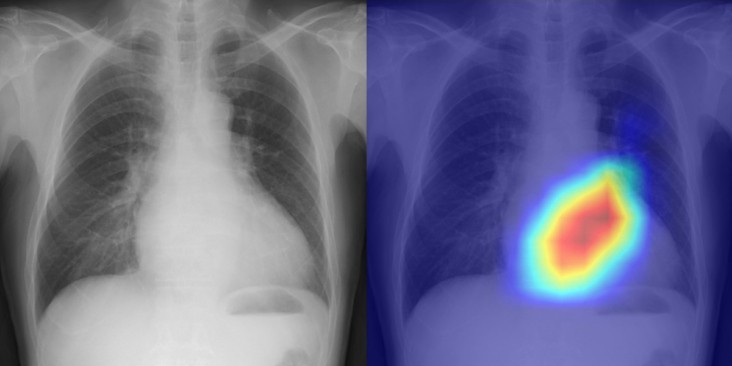

Read article: Ultralow-field MRI scanner could improve global access to neuroimaging

Ultralow-field MRI scanner could improve global access to neuroimaging

A low-cost, low-power, shielding-free, ultralow-field MRI scanner produces high-quality brain images